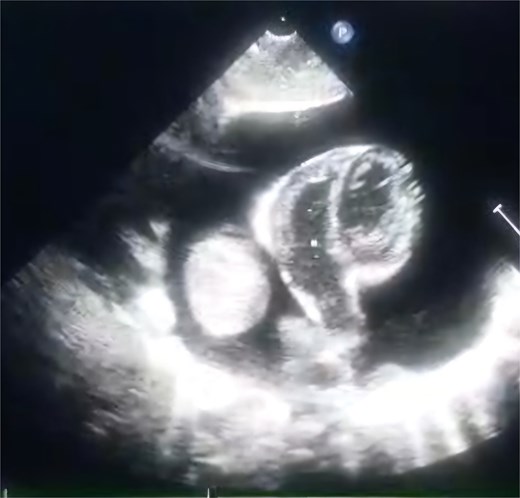

A 2-month-old female infant was admitted with respiratory distress characterized by tachypnea, and cough, along with poor feeding and systemic symptoms such as fever and episodic diaphoresis. At 25 days of age, she had previously been hospitalized for similar symptoms, during which a massive pericardial effusion was identified. Initially, an extracardiac mass was suspected. Despite undergoing two pericardiocenteses and resuscitation after two post-cardiac arrest events, her clinical status continued to deteriorate, and she was referred for urgent surgical intervention due to cardiogenic shock from pericardial tamponade. On examination, she appeared pale with respiratory distress, intercostal retractions, pulsatile hepatomegaly (2 cm), splenomegaly (1 cm), and tachycardia (160 bpm). Laboratory findings showed hyponatremia (125 mmol/L). TTE demonstrated cardiomegaly, bilateral pleural effusion, and a massive pericardial effusion measuring 24–28 mm circumferentially. A 2.7 cm mass adjacent to the anterior RA wall and atrioventricular (AV) groove was identified (Fig. 1). Due to her unstable condition, CT imaging was deferred. An emergent median sternotomy revealed a severely distended pericardium containing copious effusion (Fig. 2). Upon opening the pericardium, immediate hemodynamic improvement was observed. The mass was visualized infiltrating the RA anterior wall and AV groove (Fig. 3). Total cardiopulmonary bypass (CPB) was initiated using aortic and bicaval cannulation. Following cardiac arrest with antegrade cold blood cardioplegia, the RA was incised posterior to the tumour. The lesion extended beyond the AV groove, precluding complete excision due to anatomical constraints (Fig. 4). Subtotal (debulking) resection was performed (Figs 4 and 5), and the RA anterior wall was reconstructed with a bovine pericardial patch (Fig. 6). The patient was successfully weaned from CPB, and the remainder of the surgery was uneventful. The infant was extubated within 48 hours and discharged after a 14-day hospital stay, with subsequent TTE showing satisfactory cardiac function. Histopathological evaluation confirmed a benign capillary hemangioma characterized by lobulated reddish tissue with compact capillary proliferation, fibrous septae, and stromal hyalinization. Immunohistochemical staining was positive for CD31 and CD34, confirming endothelial origin and ruling out malignancy (Fig. 7). At one-year follow-up, the patient remained in excellent general health with no signs of recurrence.

TTE view showing the massive pericardial effusion and the mass.